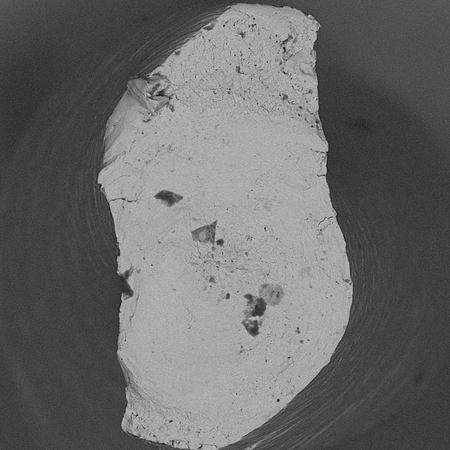

OBJETIVO: O objetivo foi avaliar, por meio de microtomografia computadorizada (micro-CT), a capacidade de modelagem e segurança de diferentes instrumentos em canais mesiais de molares inferiores após o uso a 37ºC e 20ºC. MÉTODOS: Trinta e seis molares inferiores humanos extraídos foram escaneados por micro-CT e divididos em três grupos (n=12), conforme o sistema de instrumentação: Reciproc Blue (REC), ProDesign R (PDR) e X1 Blue File (X1), subdivididos por temperatura (n=6; 20ºC e 37ºC). Após a instrumentação, os espécimes foram reescaneados e analisados quanto ao aumento de...

OBJECTIVE: The aim of this study was to evaluate, using micro-computed tomography (micro-CT), the shaping ability and safety of different endodontic instruments in mesial canals of mandibular molars after use at 37ºC and 20ºC. METHODS: Thirty-six extracted human mandibular molars were scanned by micro-CT and divided into three groups (n=12) according to the instrumentation system: Reciproc Blue (REC), ProDesign R (PDR), and X1 Blue File (X1), and further subdivided by temperature (n=6; 20ºC...